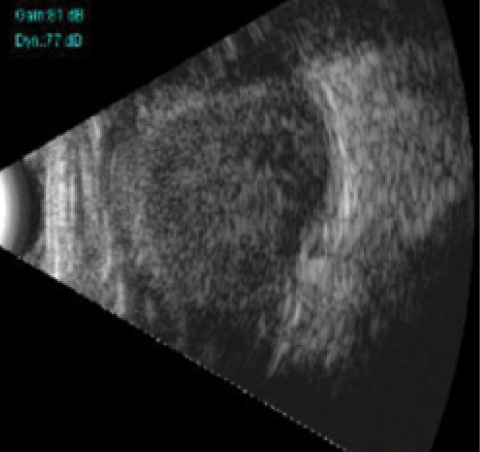

A 56-year-old woman was referred to our center with a history of a needle injury to her right eye (OD). Primary treatment had been given at a peripheral center. On examination, she had lid edema, chemosis, and subconjunctival hemorrhage OD. Additionally, the lens had been expelled into the superotemporal subconjunctival space (Figure 1). There was a mild hyphema, and the pupil was distorted and updrawn with vitreous in the anterior chamber. Fundus details were hazy due to vitreous hemorrhage. A dense suprachoroidal hemorrhage was noted on ultrasound (Figure 2). The patient’s visual acuity was light perception with faulty projection at this stage.

Figure 2. Ultrasound image shows a dense suprachoroidal hemorrhage OD.